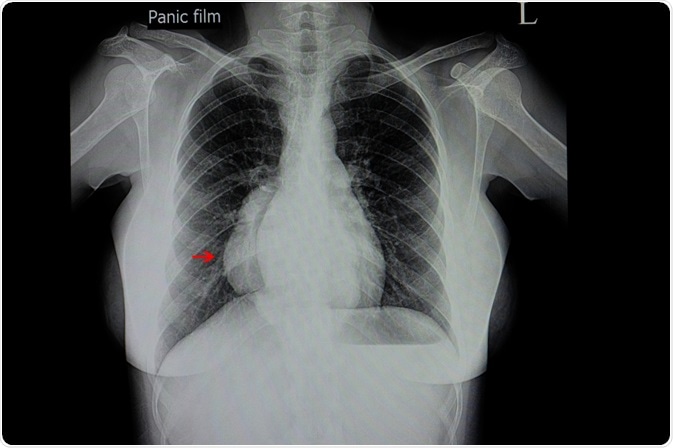

Plain chest radiography is not useful but may be helpful when alternative causes of fever are suggested (such as atelectasis or pneumonia). Likewise, pericardial or pleural effusion, pneumomediastinum, and empyema that may be a consequence of mediastinitis can also be revealed by X-ray imaging.